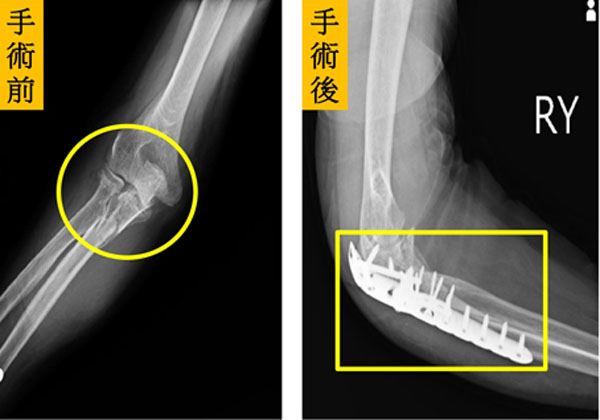

(优活健康网记者/王韵雅报导)一名70岁陈先生在家中不小心跌倒,左手手肘直接撞到地上,手肘严重变形、剧烈疼痛、活动困难,家人赶紧将陈先生送到医院急诊,X光发现患者手肘呈现粉碎性骨折还有手肘关节脱臼。急诊医师将手肘关节复位后,再安排电脑断层进行检查,发现这是令国内外骨科医师都十分头痛的“手肘恐怖三联症”(Terrible Triad Injury of Elbow)。

后续,医师除了安排桡骨头人工关节置换手术,也进行尺骨冠状突骨折固定及手肘外侧副韧带(Lateral collateral ligament ,LCL)修补手术。手术后陈先生不仅可以开心比“赞”和“OK”,2个月后手肘关节已活动自如,生活终于恢复正常。

仁爱长庚合作联盟医院运动医学中心医师徐振恒指出,医师通常会先安排手肘关节的X光检查,初步确认骨折和脱臼情况。若需更详细的评估,则会安排电脑断层扫描(Computed Tomography,CT)来协助进一步的手术规划。

徐振恒补充,治疗方法会因损伤的严重程度而有所不同,首先采取桡骨骨折复位固定、桡骨头人工关节置换、尺骨冠状突固定以及手肘外侧副韧带修补手术;更严重者,可能需要再进行内侧副韧带(Medial Collateral Ligament,MCL)修补。